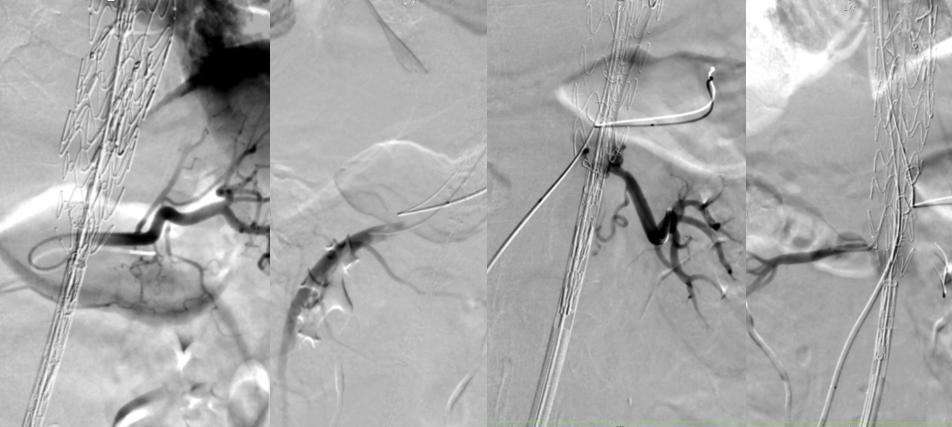

超选SMA,桥接8-100mm Viabahn,内衬8-60mm Absolute裸支架

超选CA,桥接8-100mm Viabahn

超选RRA烟囱支架,桥接6-100mm+6-50mm Viabahn

超选LRA烟囱支架,桥接6-100mm Viabahn

术后造影